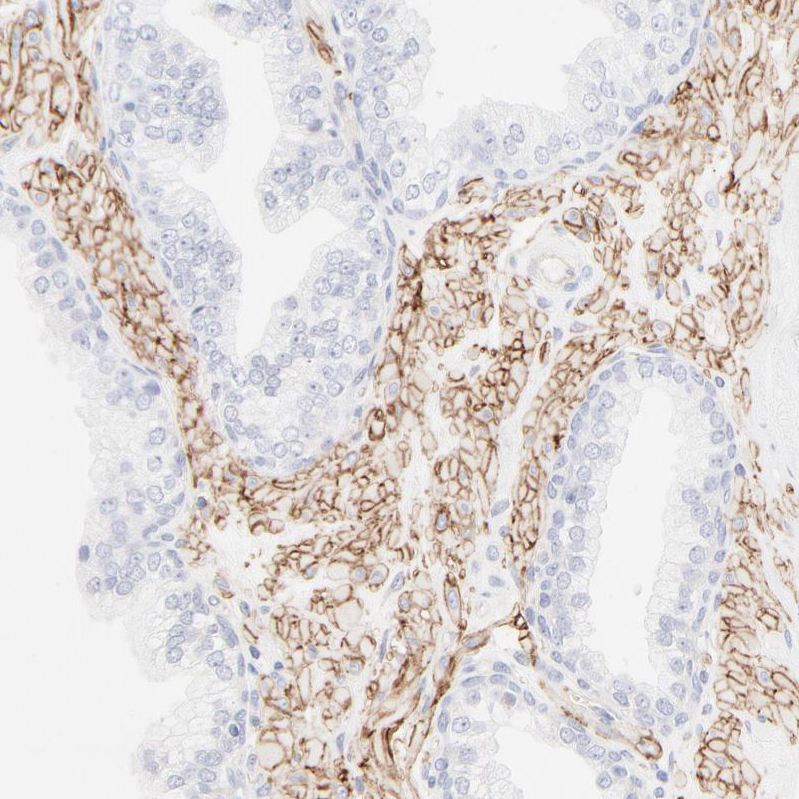

Immunohistochemistry analysis in human placenta and skeletal muscle tissues using HPA002642 antibody. Corresponding ITGA5 RNA-seq data are presented for the same tissues.